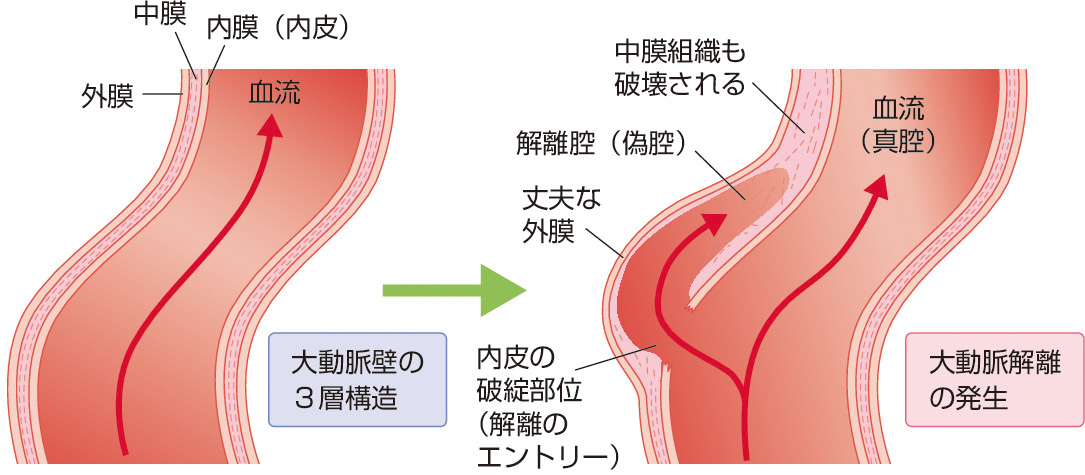

発症のメカニズム

動脈壁は内膜,中膜,外膜の3層構造からなる.高血圧や喫煙,糖尿病,脂質異常などがあると,内膜に破綻をきたし,ここが解離のエントリー (入口,はじまり) になる.丈夫な外膜が保たれつつ中膜組織の破壊が進行すると,それが解離腔 (偽腔) を形成する.こうして,解離腔 (偽腔) と本来の血流である真腔からなる大動脈解離が発生する (図1).解離を伴わずに大動脈が瘤状に拡大したものを大動脈瘤とよぶ.大動脈脈瘤に解離を合併することもあれば合併しないこともあり,大動脈解離に瘤を合併することもあればしないこともある.粥腫 (じゅくしゅ) (プラーク) によって大動脈内腔が狭小化すると,大動脈は内腔を確保しようとして代償的にその部位を拡張させる (血管リモデリング).これが大動脈瘤の原因になる.このほか,血行力学的ストレスが内膜にエントリーをつくって解離を引き起こすと考えられることから,高血圧,心拍動によるwater–hammer効果,脈圧差 (収縮期血圧と拡張期血圧の差),ずり応力 (血流の方向に内腔面から血管に向かってかかる力),乱流,狭窄後のジェット血流などが,大動脈瘤や大動脈解離の原因と考えられる.